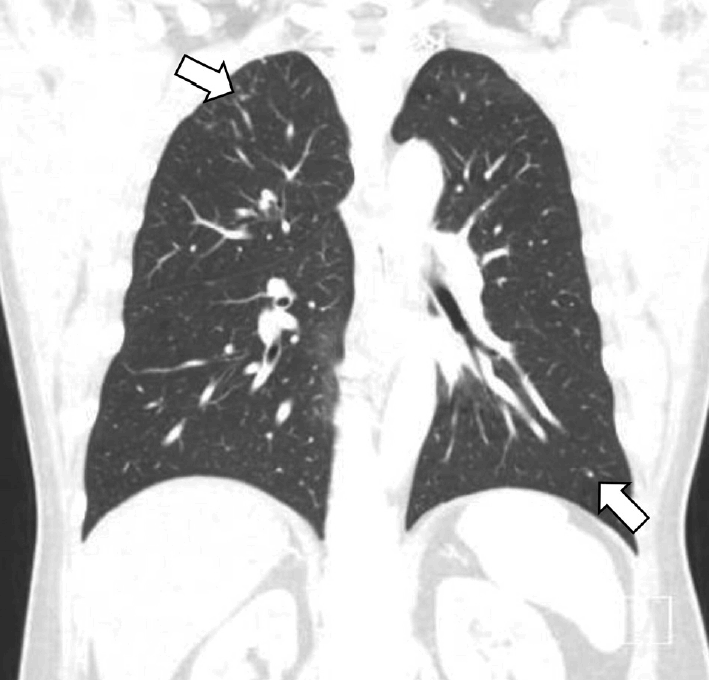

수술 후 1달 째 환자의 경부 종물 크기가 증가하여 경부 전산화단층촬영을 시행하였고, 양측 경부 구역 1b, 2, 3과 좌측 경부 5b, 이하선 내측에서 비괴사성 저음영의 림프절병증이 확인되었다(Fig. 4). 임파선 절제 생검에서도 비인두 종물의 조직소견과 같은 비건락성 육아종으로 사르코이드증에 가까운 소견을 보였으나 수술 후 40일 째에 비인두 조직 배양검사에서 결핵균의 배양이 확인되어 항결핵제 이소니아지드(isoniazid), 에탐부톨(ethambutol), 리팜핀(rifampin), 피라진아미드(pyrazinamide) 복용을 시작하였다. 흉부 단순촬영상에서 폐결핵 소견은 보이지 않았고, 환자가 알고 있는 결핵 병력은 없었으나 QuantiFERON-TB 검사상 양성소견이었다. 이때 흉부 전산화단층촬영을 권유하였으나 환자가 거부하여 수술 후 6개월째에 시행한 결과, 폐 우상엽과 좌하엽에서 경계가 뚜렷하지 않은 불분명하고 비특이적인 미세결절성 침윤이 확인되었다(Fig. 5). 결핵과 사르코이드증이 정확히 감별되지 않았으나 호흡기내과와 협진으로 비인두 조직 배양검사상 결핵균이 확인되었기에 결핵에 의한 병변으로 판단하여 치료하는 것이 적절하다고 생각하였다.

Chest CT scan findings. Equivocal ill-defined micronodular infiltration at right upper lobe apex and left lower lobe were found (arrows).